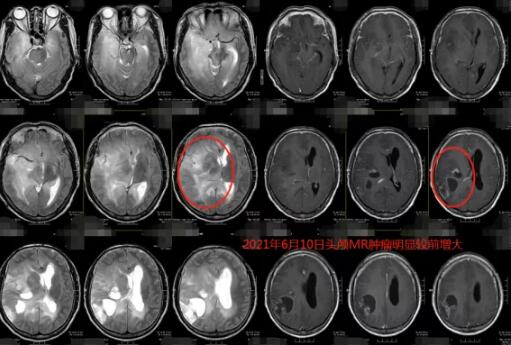

6月初,患者住进了我院神经外五科。此时,他的头颅MR检查提示:颅内脑实质多发病变,以右侧大脑半球较著,考虑弥漫性星形细胞瘤可能性大(其中右侧基底节区-放射冠、右侧顶叶占位性病变)。

对比1年前在我院做的影像资料,病灶范围明显增大,几乎“占据”整个右半边脑!